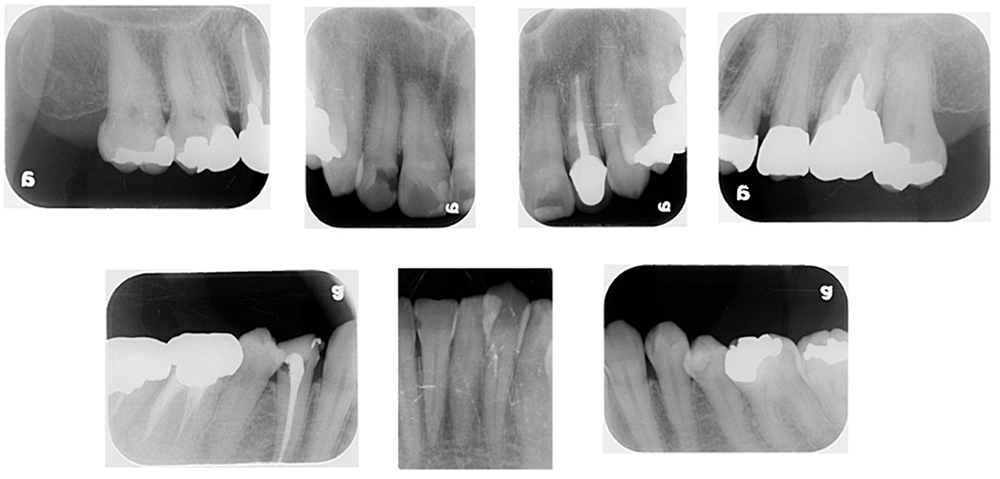

レントゲン検査

歯や歯を支えるあごの骨の状態を調べます。

肉眼でみる情報とは別に確認しにくいムシ歯や歯周病の状態を判断できます。